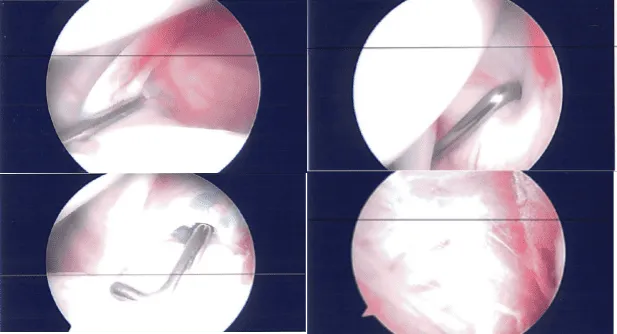

Un portal posterior de entrada estaba formado por el hombro. El endoscopio se introdujo en la articulación glenohumeral. Se examinó la articulación glenohumeral y se encontró cierto deshilachamiento de la superficie articular del manguito rotador, así como deshilachamiento del labrum glenoideo anterosuperior y hasta el tendón del bíceps.

El tendón del bíceps estaba intacto. El IGHL, MGHL, subescapular, labrum inferior y posterior estaban intactos. Se tomaron y guardaron fotos.

El desbridamiento del labrum glenoides y del manguito rotador se realizó mediante una afeitadora. El cierre se hizo con nylon. Se realizó el vestir. El brazo izquierdo fue colocado en un cabestrillo para el hombro y el paciente fue extubado y trasladado a la unidad de recuperación en estado estable.